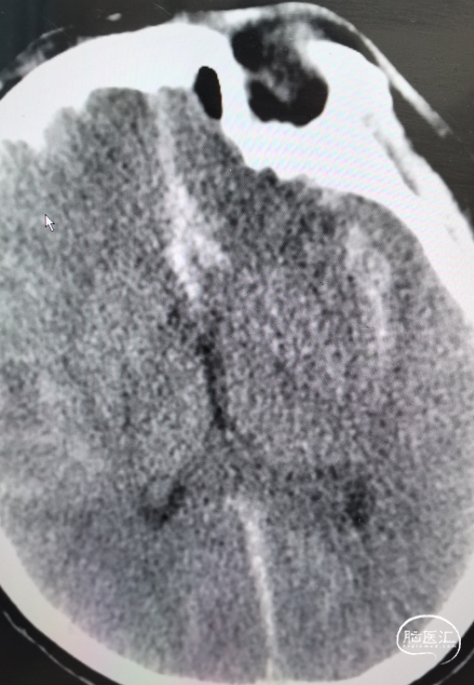

影像信息

头颅CT显示:额叶蛛网膜下腔出血。